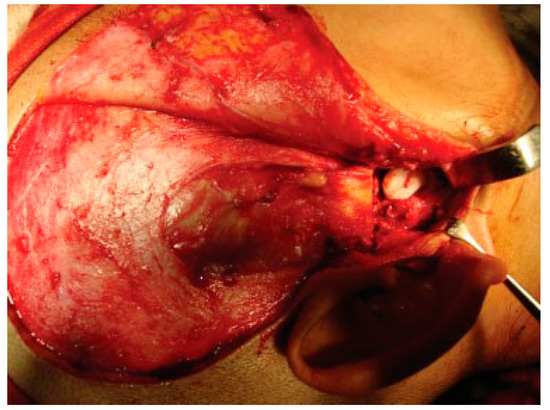

Figure 5. Intraoperative passive mouth opening.

Reconstruction of the TMJ after release of ankylosis assumes paramount importance in terms of restoration of facial form and function. The goals of treatment in all the patients were the release of ankylotic mass, restoration of normal jaw form and function, symmetric growth of the mandible in children, and most importantly the prevention of reankylosis. All interpositional arthroplasties are to some extent the autogenous reconstruction of the morbid ankylotic TMJ after resection of the ankylotic mass. Merriam Webster Dictionary defines reconstruction as the act or process of building something that was damaged or destroyed again. Reconstructive surgery refers to a procedure whose goal is intended to restore form and function in structures deformed or damaged by disease, congenital anomaly, tumor, trauma, or infection (Farlex Partner Medical Dictionary Farlex 2012). The treatment of TMJ ankylosis is individualized based on the severity of ankylosis, age of the patient, and other patient factors. We have outlined our experience following Kaban’s protocol in the management of TMJ ankylosis. It is of paramount importance to obtain passive and maximal mouth opening using this protocol in terms of adequate resection and ipsilateral or contralateral coronoidectomy whenever required followed by aggressive physiotherapy (Figure 5 and Figure 6). Physiotherapy was started on third day postoperatively using Heister mouth gag five times a day during the hospital stay of the patient. This device was purchased by the patient after discharge from the hospital for physiotherapy at home. The MIMO and excursive movements were recorded at various follow-ups for all the patients. No intermaxillary fixation/elastics were applied to any of the patients in the series.